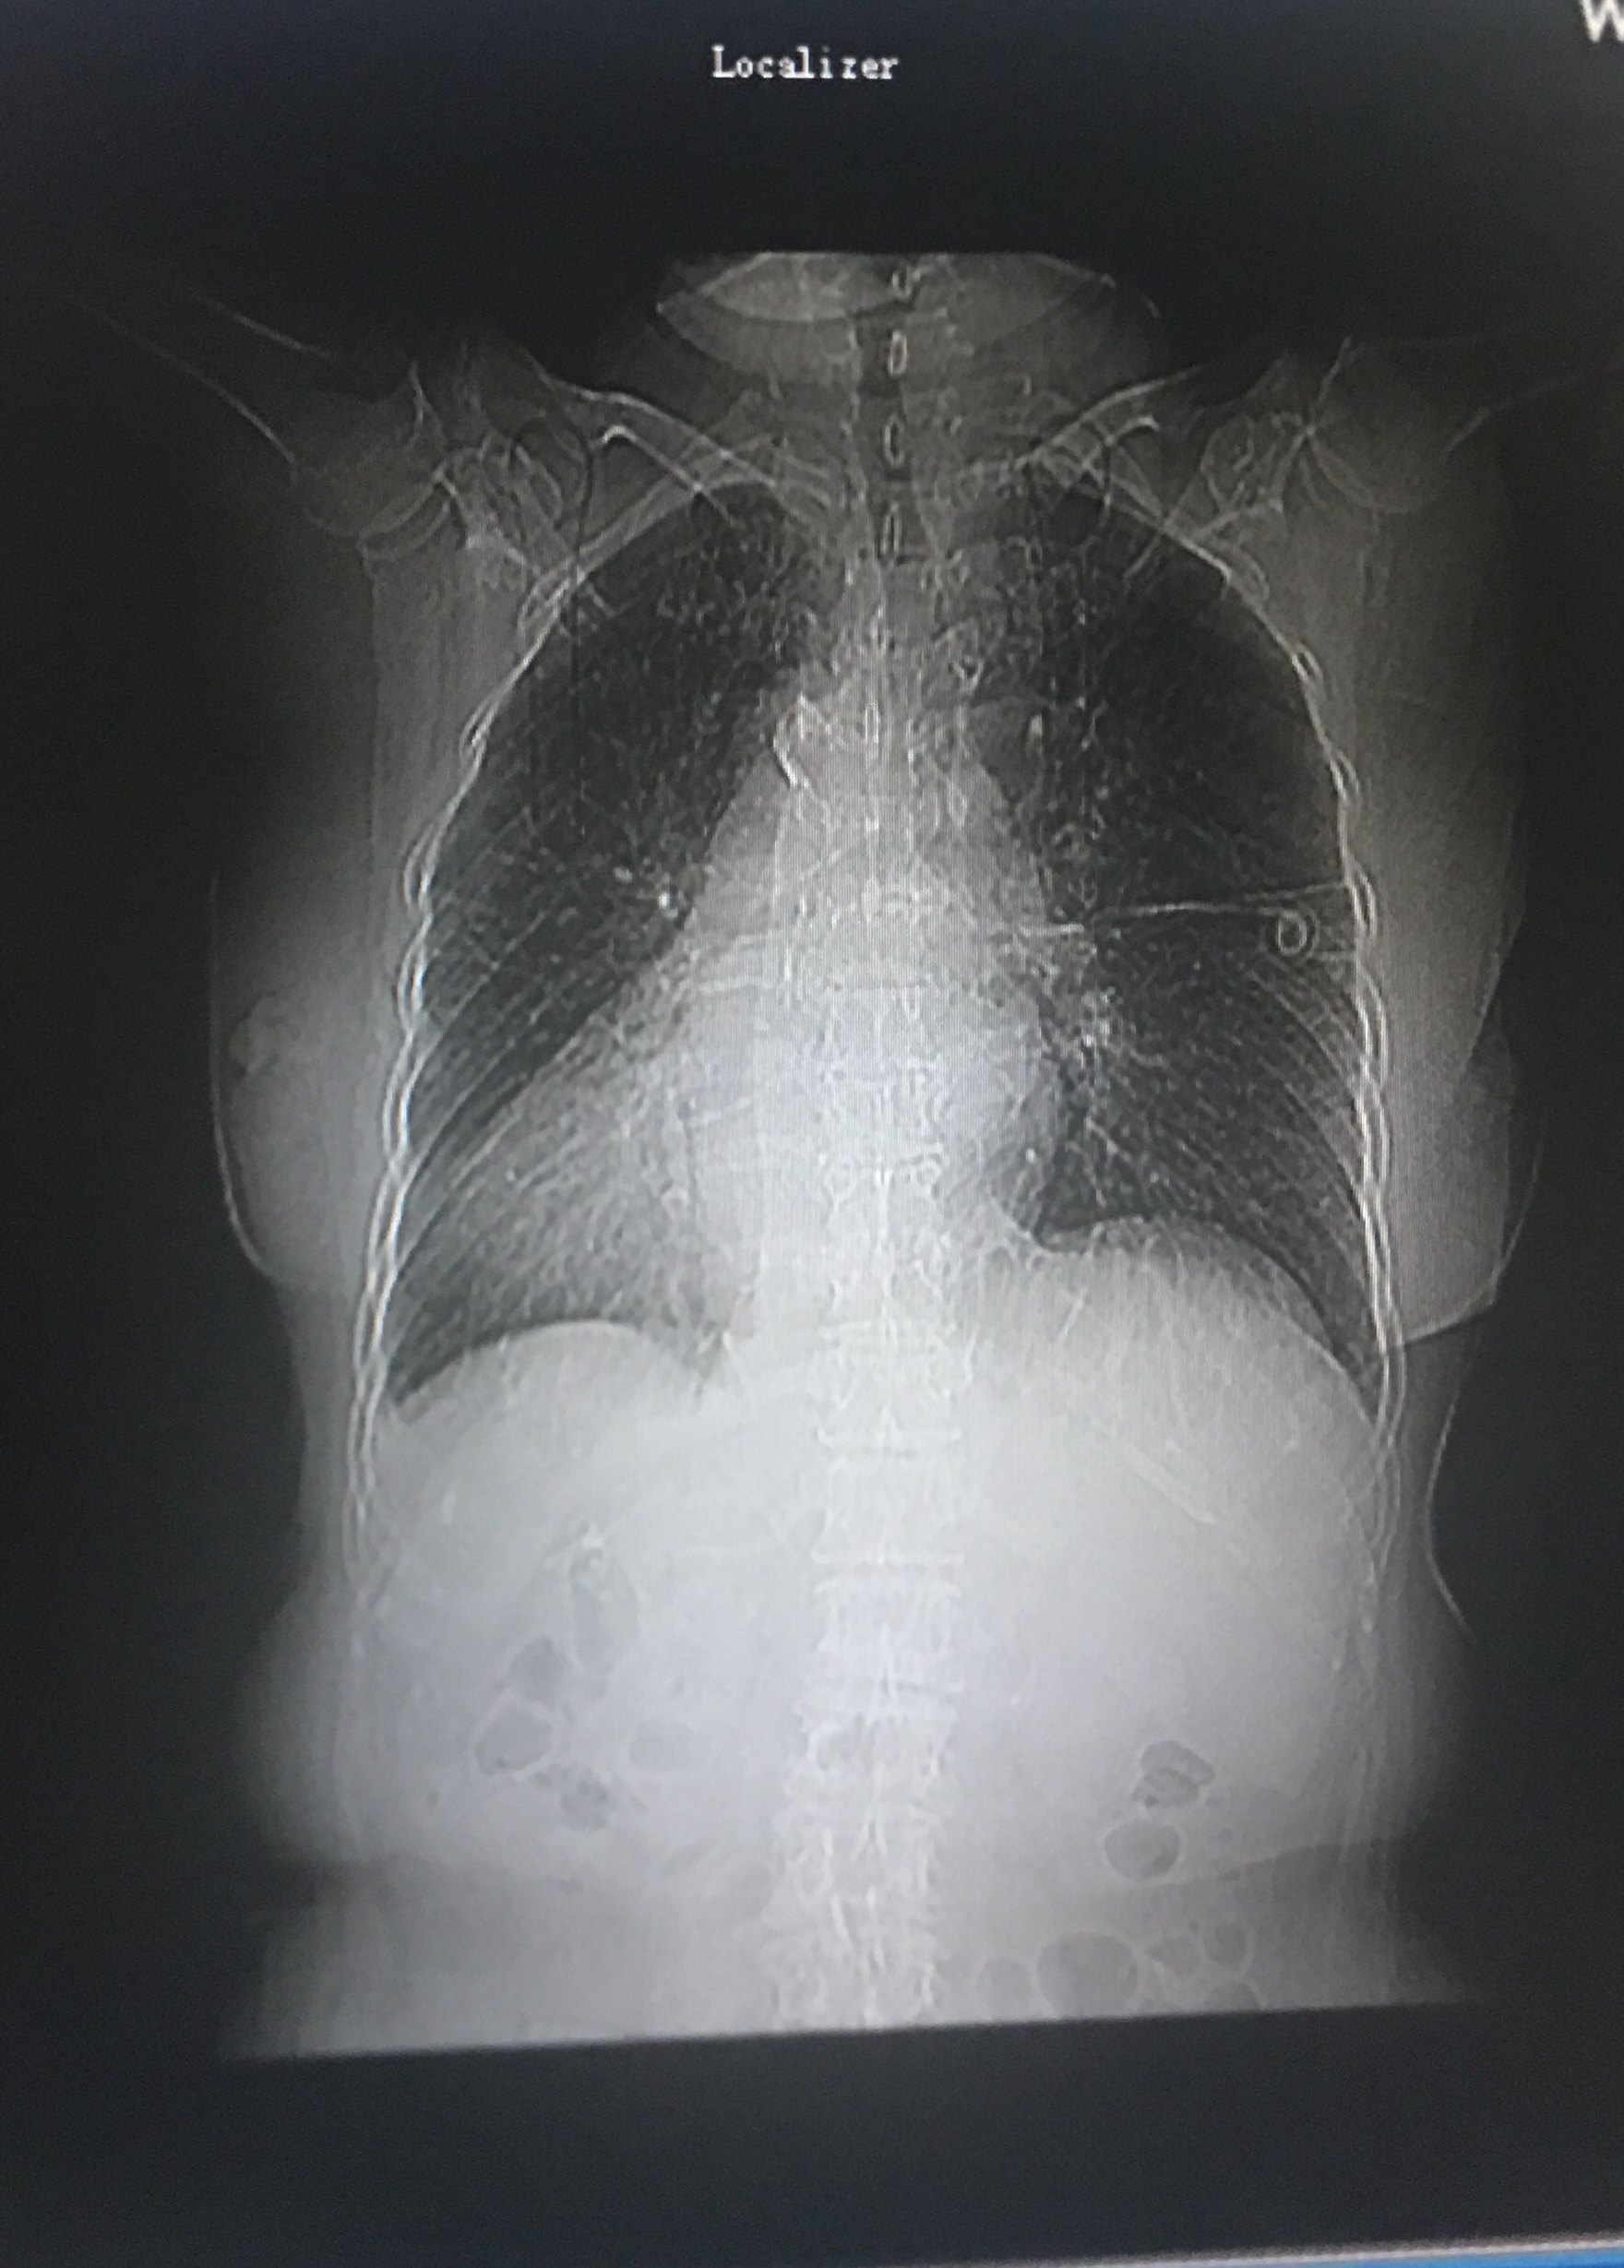

男,51岁; 确诊幽门癌肝转移,腹腔淋巴结转移半年; 不全性上消化道梗阻

图片尺寸2000x3537